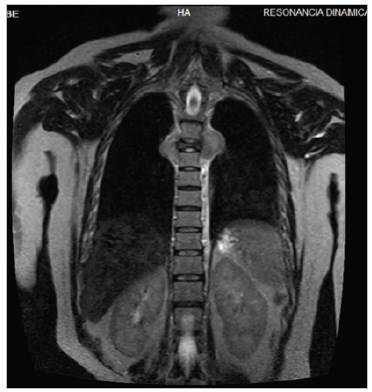

Mujer de 44 años con antecedente de artritis reumatoide. Inició hace cuatro años con dolor en región dorsal y lumbar, pérdida de peso no significativa, sin fiebre, parestesias y debilidad progresiva en miem bros inferiores hasta llegar a la inmovilización. A la exploración física paraplejia de miembros inferiores y reflejos osteotendinosos disminui dos, sin adenomegalias ni masas. Laboratorios sin anormalidades. La resonancia magnética de columna dorsal y lumbar mostró lesión ósea blástica en T5 que afecta cuerpo vertebral, pedículo, apófisis transversa y unión costo vertebral derecha condicionando disminución del diáme tro intervertebral (Figuras 1 y 2). Biopsia vertebral con hallazgos de osteomielitis crónica asociada a estructuras micóticas compatibles con coccidioides (Figura 3). Recibiendo anfotericina b desoxicolato durante dos semanas, hidratación intravenosa, presentando mejoría, egresándose con itraconazol y control por infectología. La coccidioidomicosis es una infección fúngica capaz de producir osteomielitis siendo la columna lumbar el sitio principal, pudiendo complicarse con abscesos paravertebrales 1,2.